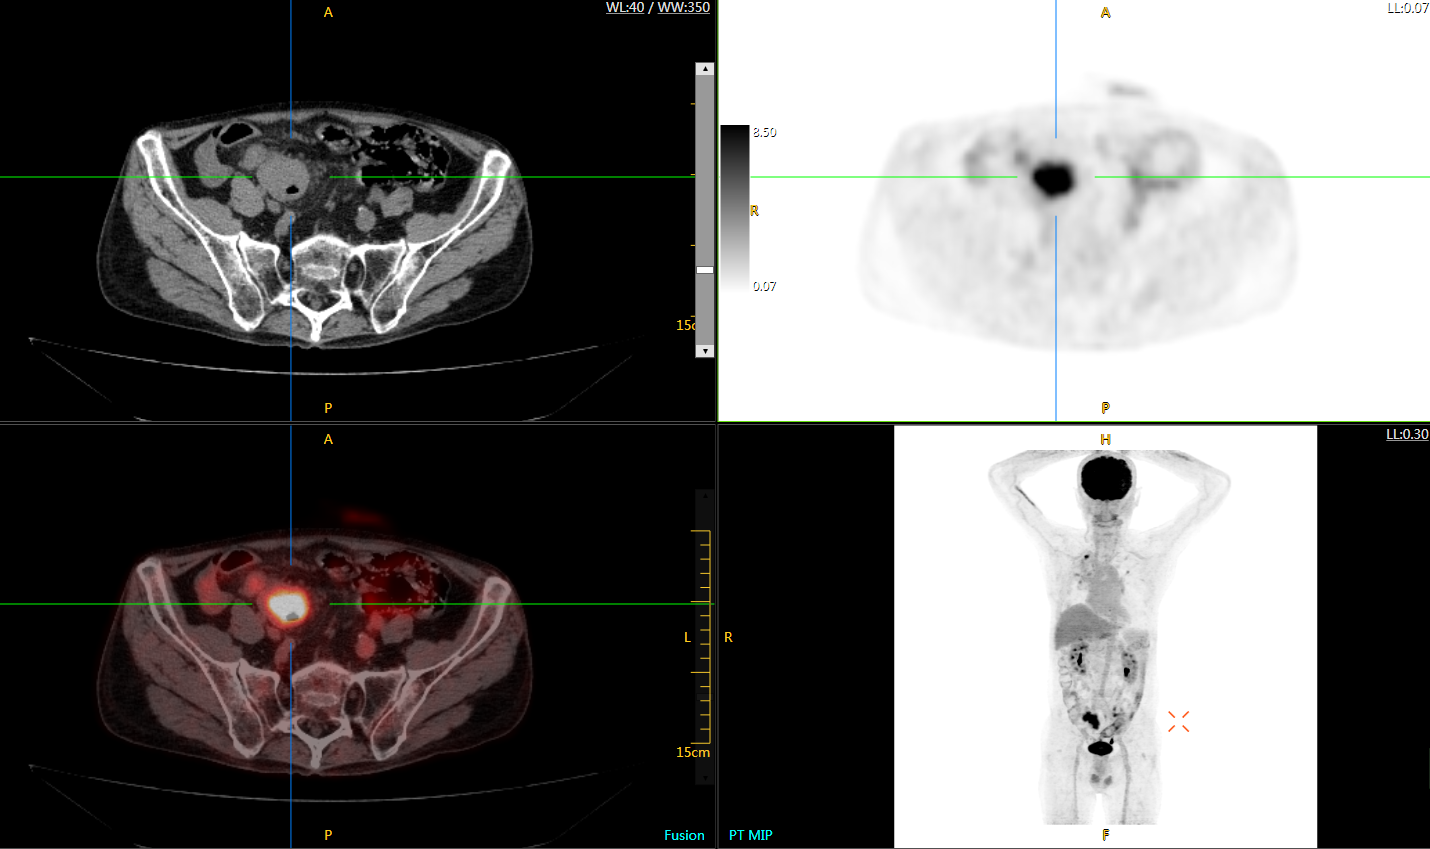

直腸癌

男,45歲,直腸癌術(shù)后9個(gè)月,發(fā)現(xiàn)肺占位

臨床診斷:直腸區(qū)術(shù)后改變,復(fù)發(fā)伴骶骨受累,雙肺多發(fā)轉(zhuǎn)移